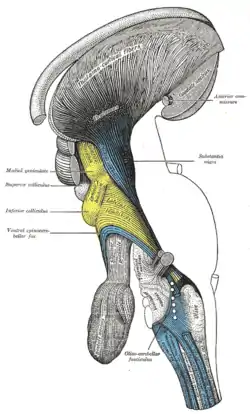

Dissection of brain-stem. Lateral view. Deep dissection of brain-stem. Lateral view.

Deep dissection of brain-stem. Lateral view. Deep dissection of brain-stem. Lateral view.